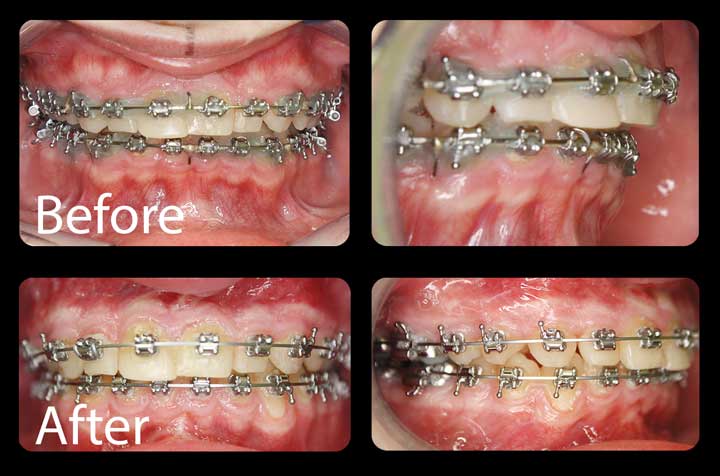

Corrective Jaw Surgery

Computer-planned orthognathic surgery to correct jaw misalignment, restore bite function, and achieve facial harmony. Dr. Antipov treats underbites (Class III malocclusion), overbites (Class II malocclusion), open bites, crossbites, facial asymmetry, and obstructive sleep apnea. Procedures include Le Fort I osteotomy (single-piece and 3-piece), bilateral sagittal split osteotomy (BSSO), genioplasty (chin repositioning), maxillomandibular advancement, and double jaw surgery. Every case uses 3D virtual surgical planning for millimeter-precise results.